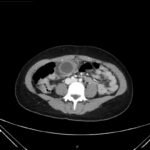

An 18-year-old female presented to the emergency department (ED) with two days of right lower quadrant pain and associated nausea and emesis. After relevant information was gathered and with physical exam findings of a tender right lower quadrant, positive psoas sign, positive Rovsing sign, and pain with right heel tap, the patient was presumed to have appendicitis. However, imaging contradicted the initial leading diagnosis and revealed a markedly distended, hydropic gallbladder with its tip near the umbilicus. Findings of the distended gallbladder with marked wall thickening and pericholecystic fat stranding and edema confirmed acute cholecystitis, and the patient was taken by general surgery for cholecystectomy. Together, this unusual presentation and this unexpected diagnosis shine light upon another facet of the hydropic gallbladder while also serving as a salient reminder to contemplate a broad differential regardless of seemingly classic presentations of illnesses.